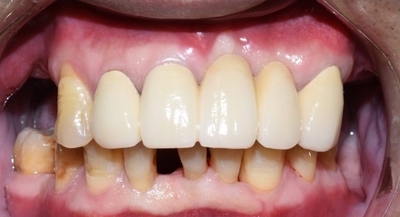

50대 초반 남자환자분이셨는데요, 앞니가 흔들린다는 것을 이유로 저희 치과를 처음 방문하셨습니다.

물론 어금니도 없어서 문제였지만, 보이는 앞니가 이러면 사회생활에 문제가 있죠.

![[치과브릿지케이스] 앞니가 너무 많이 흔들려서 발치해야 할 것 같아요 관련 이미지 1](https://pub-9f2bb3498faf4d1d8714b41df24753e3.r2.dev/content/clinics/archive/rseeanjxfu/naver_blog/yonseiyegam/assets/by_hash/4541c07cf9d9ef2d428355cf98e301aebe7bfba9362b96ea1f637bd2a5322e3f.jpg)